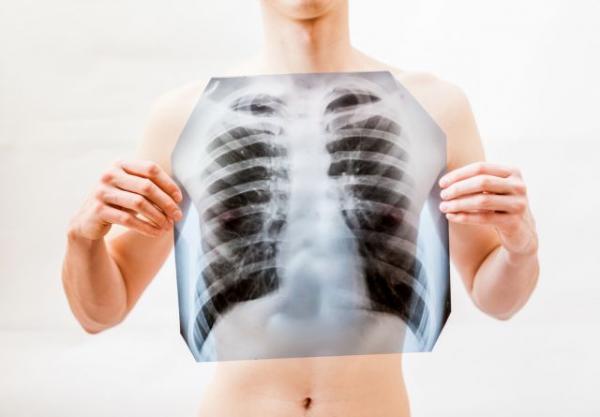

Είναι η όχι αυτοί οι πνεύμονες ασθενούς με κοροναϊό; – Σάλος στο διαδίκτυο, τι ισχύει τελικά

Αλαλούμ έχει προκαλέσει η φωτογραφία με τις δύο ακτινογραφίες που ανήρτησε στο Facebook ακτινολόγος από το ΚΑΤ και που σε αυτήν αποτυπώνεται η ραγδαία επιδείνωση που προκαλεί ο κοροναϊός στους ασθενείς.